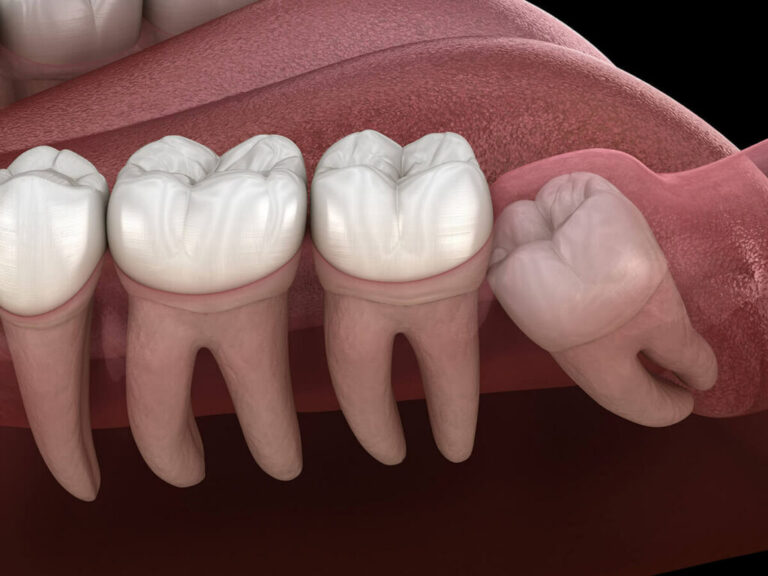

Οι φρονιμίτες είναι τα τέσσερα τελευταία δόντια που βρίσκονται στις γωνίες της άνω και κάτω γνάθου. Είναι τα τελευταία δόντια που εμφανίζονται στο στόμα και συνήθως είναι τα λιγότερο χρήσιμα, αφού οι διατροφικές συνήθειες έχουν εξελιχθεί και η σύγχρονη διατροφή δεν απαιτεί τόσο δυνατά γομφία όπως παλαιότερα.

Σε πολλές περιπτώσεις, οι φρονιμίτες δεν έχουν αρκετό χώρο για να αναπτυχθούν σωστά, με αποτέλεσμα να προκαλούν προβλήματα όπως πόνο, φλεγμονή, ή ακόμα και ζημιά στα διπλανά δόντια.

Έλλειψη χώρου: Σε πολλές περιπτώσεις, οι φρονιμίτες δεν έχουν αρκετό χώρο για να αναπτυχθούν πλήρως και μένουν μερικώς εγκλωβισμένοι στα ούλα ή το κόκκαλο, προκαλώντας πόνο και ερεθισμό.

Πίεση στα διπλανά δόντια: Όταν οι φρονιμίτες προσπαθούν να αναπτυχθούν σε περιορισμένο χώρο, μπορεί να πιέσουν τα διπλανά δόντια, προκαλώντας ευθυγράμμιση ή ζημιά.